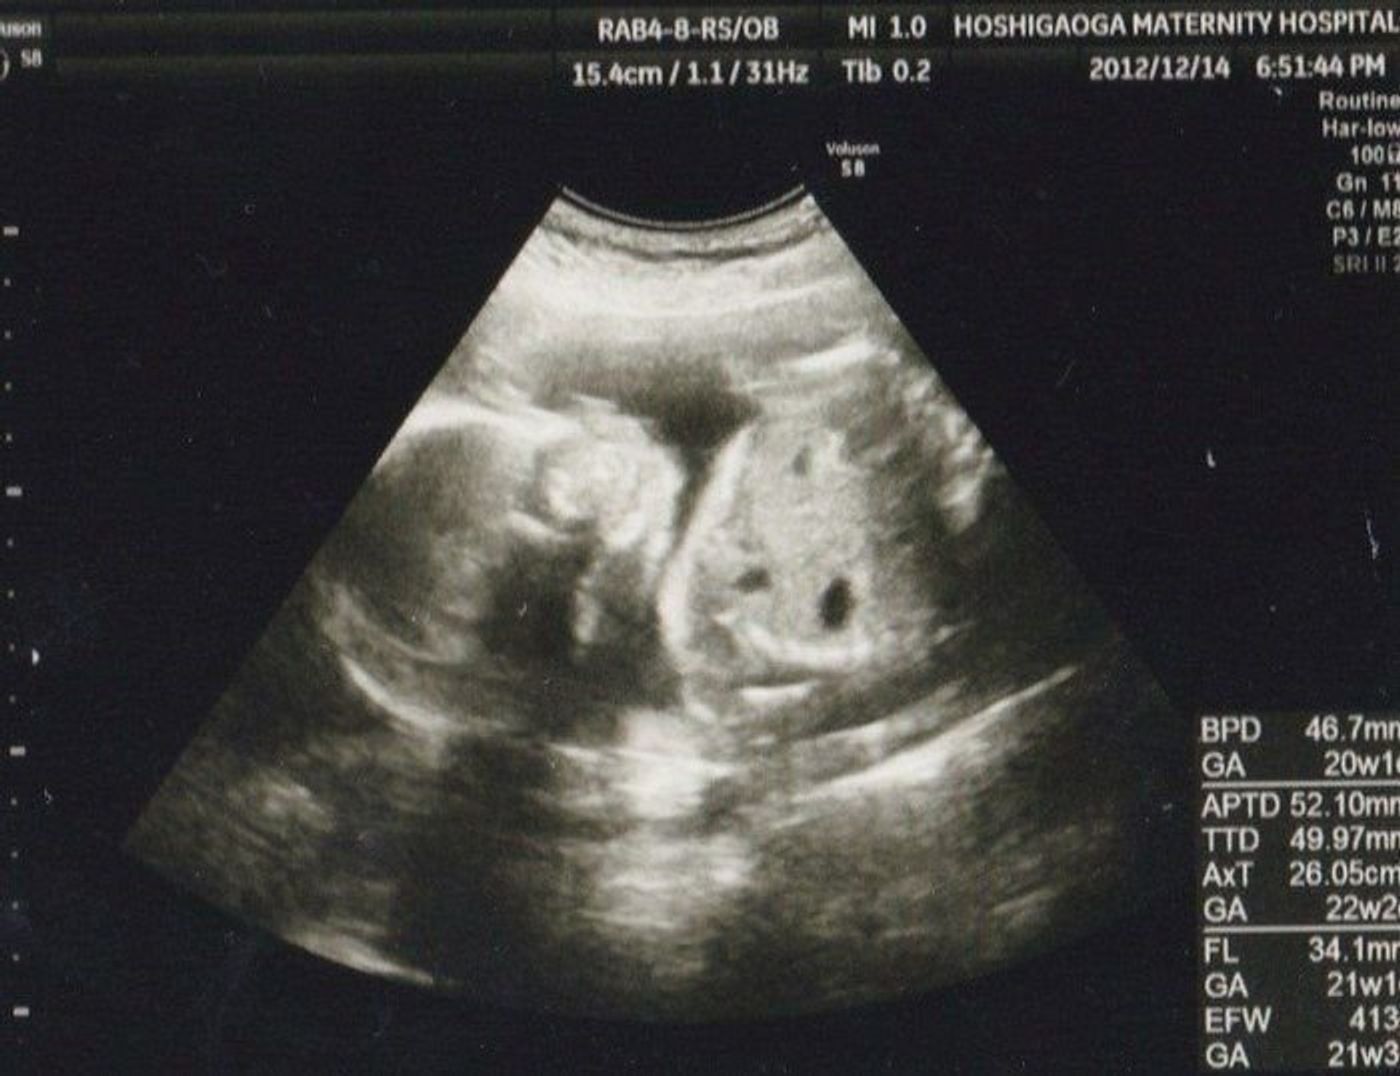

21週 赤ちゃん 何してるのギャラリー

各画像をクリックすると、ダウンロードまたは拡大表示できます

![]() 妊娠21週目 21w0d 6d のエコー写真とエピソード 妊娠6ヶ月 Cozre コズレ 子育てマガジン | ![]() 妊娠21週目 21w0d 6d のエコー写真とエピソード 妊娠6ヶ月 Cozre コズレ 子育てマガジン | ![]() 妊娠21週目 21w0d 6d のエコー写真とエピソード 妊娠6ヶ月 Cozre コズレ 子育てマガジン |